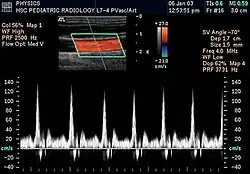

Doppler tipo espectral da carótida comum

A informação Doppler é representada graficamente com um Doppler espectral, ou como uma imagem utilizando Doppler direcional ou Doppler de potência (Doppler não direcional). A frequência Doppler enquadra-se na gama audível e é representada por altifalantes estéreo, produzindo um som pulsante distinto, embora sintético.

O Doppler colorido é essencialmente o sistema informático integrado no aparelho de ultrassons. Atribui unidades de cor dependendo da velocidade e direção do fluxo sanguíneo. Por convenção, o vermelho é atribuído ao fluxo em direção ao transdutor e o azul ao fluxo em direção oposta.